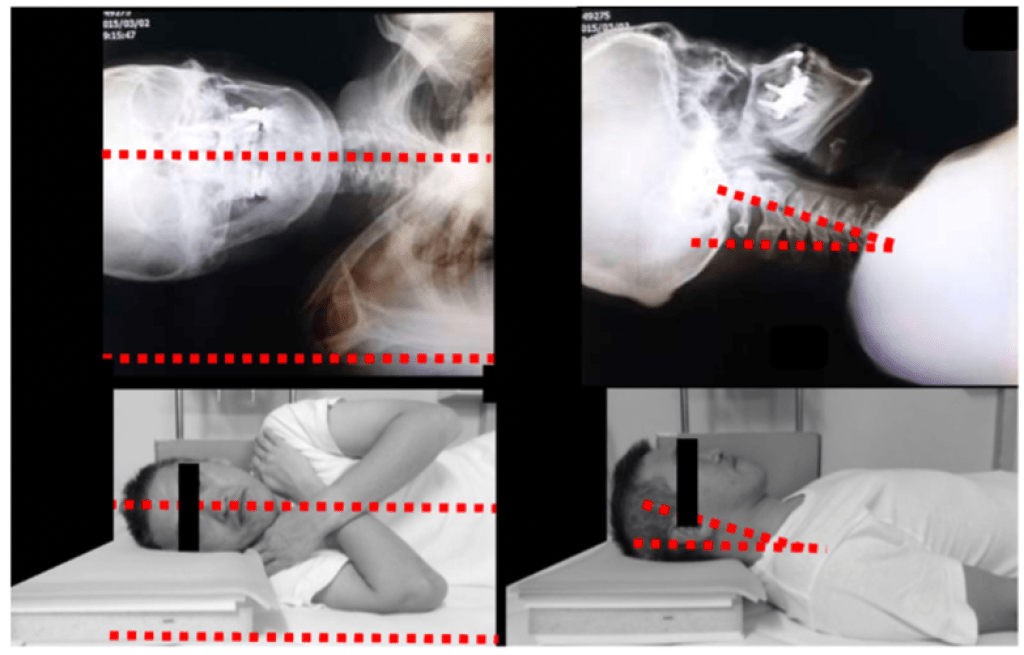

With so many pillows on the market, and so many variables to choose from, it can be hard to know where to start in finding the ideal pillow! Through my reading on this topic, I also learned more about pillow options and variables to consider when in search of your ideal pillow. The main factors to consider are pillow shape, material, and height. Generally, the position that is recommended in order to reduce tension on neck and shoulder muscles and strain on spine structures is a neutral spine (Lei, 2021; see picture below from Yamada, 2023):

To start off this discussion, let’s acknowledge that the majority of people sleep on their back (i.e., supine) or on their side (Lei, 2021). However, most people do not adopt just one of these positions but switch back and forth throughout a nights sleep. From one study, it was found that people without pain typically switch between these two positions an average of 24 times per night! (Cai, 2015). Given that people are switching so often between these two positions, it makes sense some of the research findings and best variables for the above factors:

- Height: This seems to be the most robust factor that has been studied and recommendations from the research in this area are that most pillows on the market are TOO HIGH for optimum neck position and comfort. Try for a pillow with “low loft” between 8-12cm high. The trick to this recommendation is to find a height that provides for the best head and neck position in both supine and sidelying (remember that most people switch often between these two positions). Within the recommended range above (8-12cm), if you think you will spend more time in supine a slightly flatter pillow is best and if you think that side lying is where you want to be most of the time then a slightly higher height will better support neutral spine position.